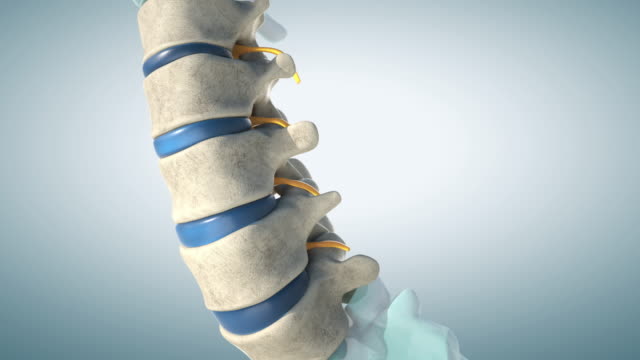

1. 척추 고정을 통한 치료

척추 고정을 통한 치료는 척추를 다시 원래 자리로 돌리는 것이 목표입니다. 이러한 치료는 전방 정의종을 통해 시행됩니다. 이 방법은 통증을 완화하는 데 효과가 있으며, 종종 통증이 사라지는 데 몇 달이 걸릴 수 있습니다. 그러나 이 치료는 재발할 가능성이 높습니다.

2. 수술적 치료

만약 척추의 상태가 매우 심각하거나 전방 전위가 지속적으로 재발하는 경우, 수술적 치료가 고려될 수 있습니다. 이러한 수술은 허리나 배꼽 지역을 절개하여 척추를 원래 위치로 돌리는 방법으로 진행됩니다. 이 치료 방법은 보다 지속적인 결과를 제공할 수 있으며, 통증 완화와 함께 기능을 회복하는 데 도움이 됩니다.